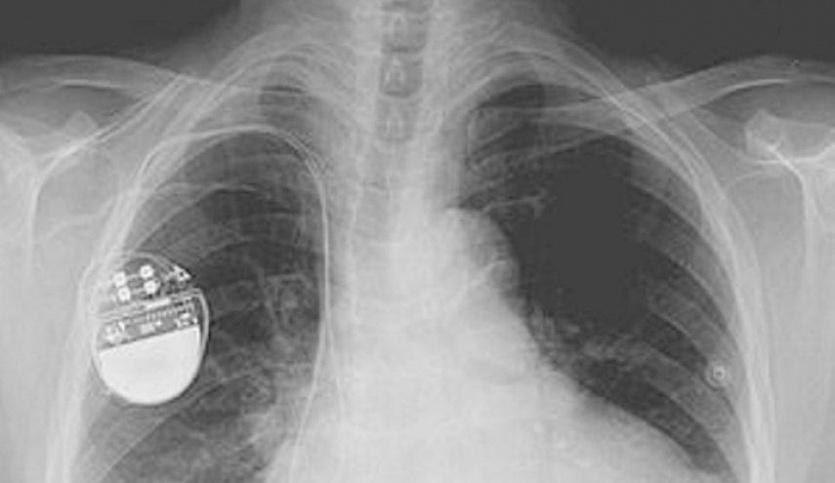

الهاكرز يمكنهم قتل مرضى القلب بإيقاف أجهزة تنظيم ضربات القلب

حذرت تقارير جديدة من أن الهاكرز يمكنهم قتل عدد من المرضى عن طريق إيقاف أجهزة تنظيم ضربات القلب أو مضخاته.

وأكد تقرير الأكاديمية الملكية للمهندسين أن عدد أجهزة الرعاية الصحية المعرضة للقرصنة في تزايد، وهي بمثابة بوابة للفيروسات التي يمكن أن تشل عمل المؤسسات الصحية الوطنية أو الإدارات الحكومية.